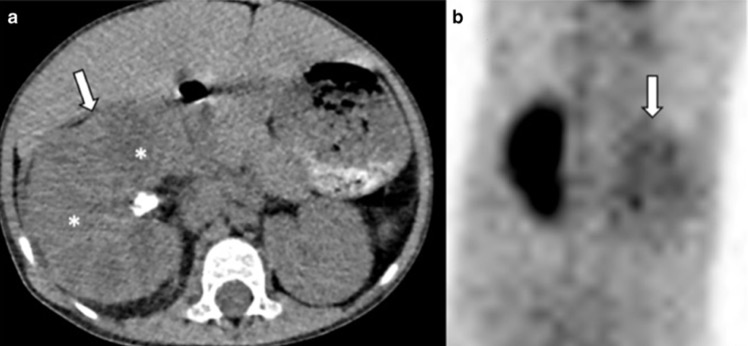

- Sarcoïdose rénale